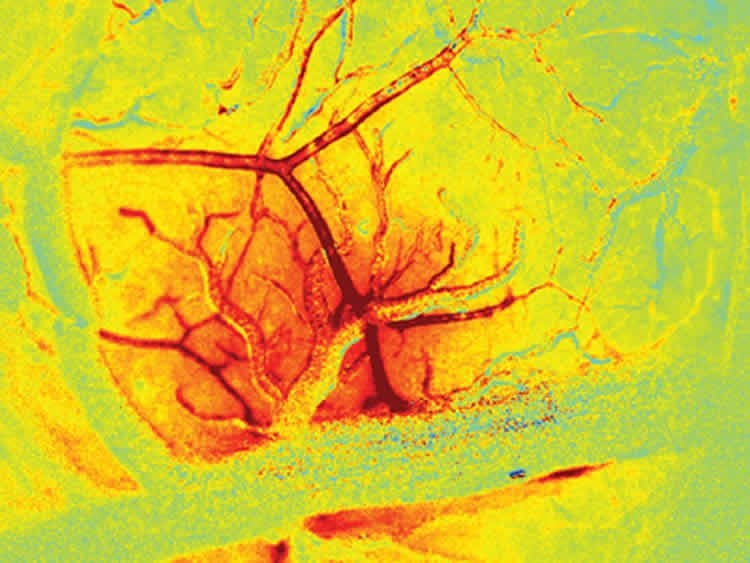

To tease apart the role of endothelial signaling in the living brain, they had to develop new ways to both image the brain at very high speeds, and also to selectively alter the ability of endothelial cells to propagate signals within intact vessels. The team achieved this through a range of techniques that use light and optics, including imaging using a high-speed camera with synchronized, strobed LED illumination to capture changes in the color, and thus the oxygenation level of flowing blood. Focused laser light was used in combination with a fluorescent dye within the bloodstream to cause oxidative damage to the inner endothelial layer of blood brain arterioles, while leaving the rest of the vessel intact and responsive. The team showed that, after damaging a small section of a vessel using their laser, the vessel no longer dilated beyond the damaged point. When the endothelium of a larger number of vessels was targeted in the same way, the overall blood flow response of the brain to stimulation was significantly decreased.

Image Source: The images are credited to Elizabeth Hillman and are adapted from the Columbia University press release